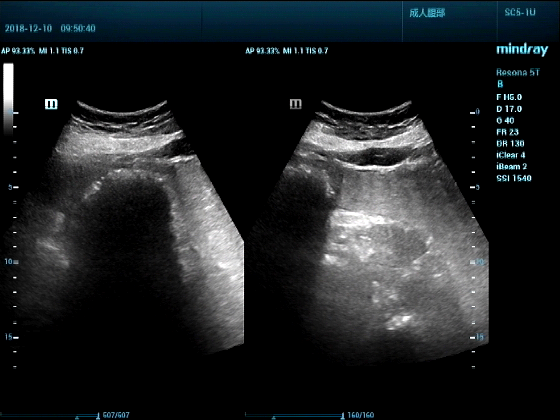

病例一:女,53岁,胃部不适一周来诊

超声可见:胃腔内见一小鸡蛋大强回声团块,后方伴强声影,位置活动。

问及病史吃山楂,柿子。

超声提示:结合临床考虑胃结石,治疗后复查